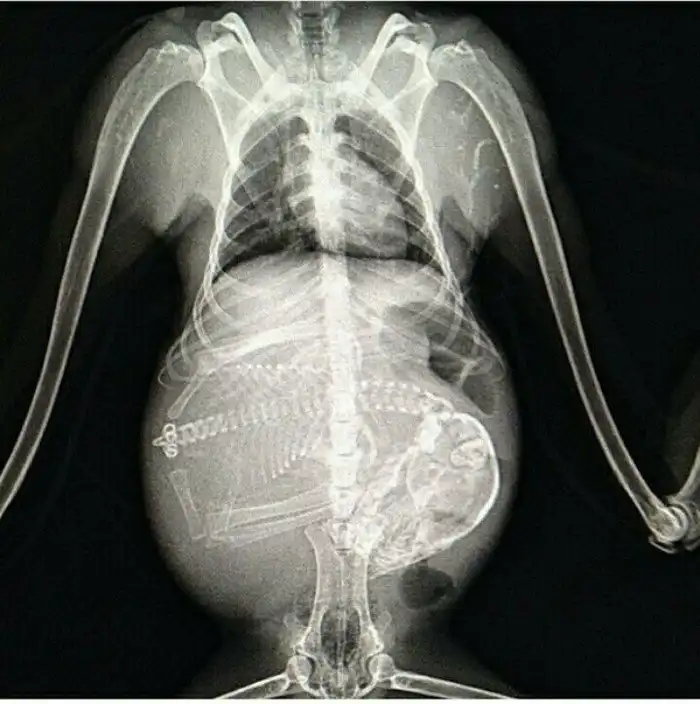

Специалисты, которые по долгу своей работы наблюдают животных, готовых принести потомство, поделились этими удивительными рентгеновскими и ультразвуковыми снимками.

1. Беременная собака